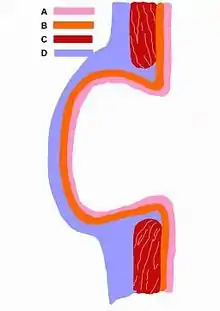

| Schematic drawing of a false diverticulum. A - mucosa; B - submucosa; C - muscularis; D - serosa and subserosa | |

In medicine or biology, a diverticulum is an outpouching of a hollow (or a fluid-filled) structure in the body.[1] Depending upon which layers of the structure are involved, diverticula are described as being either true or false.[2]

Diverticula are described as being true or false depending upon the layers involved:

- False diverticula (also known as "pseudodiverticula") do not involve muscular layers or adventitia. False diverticula, in the gastrointestinal tract for instance, involve only the submucosa and mucosa, such as Zenker's diverticulum.[2] False diverticula are typically synonymous with pulsion diverticula, which describes the mechanism of formation as increased intraluminal pressure.

- True diverticula involve all layers of the structure, including muscularis propria and adventitia, such as Meckel's diverticulum.[2] True diverticula are typically synonymous with traction diverticula, which describes the mechanism of formation as pulling forces external to the structure.